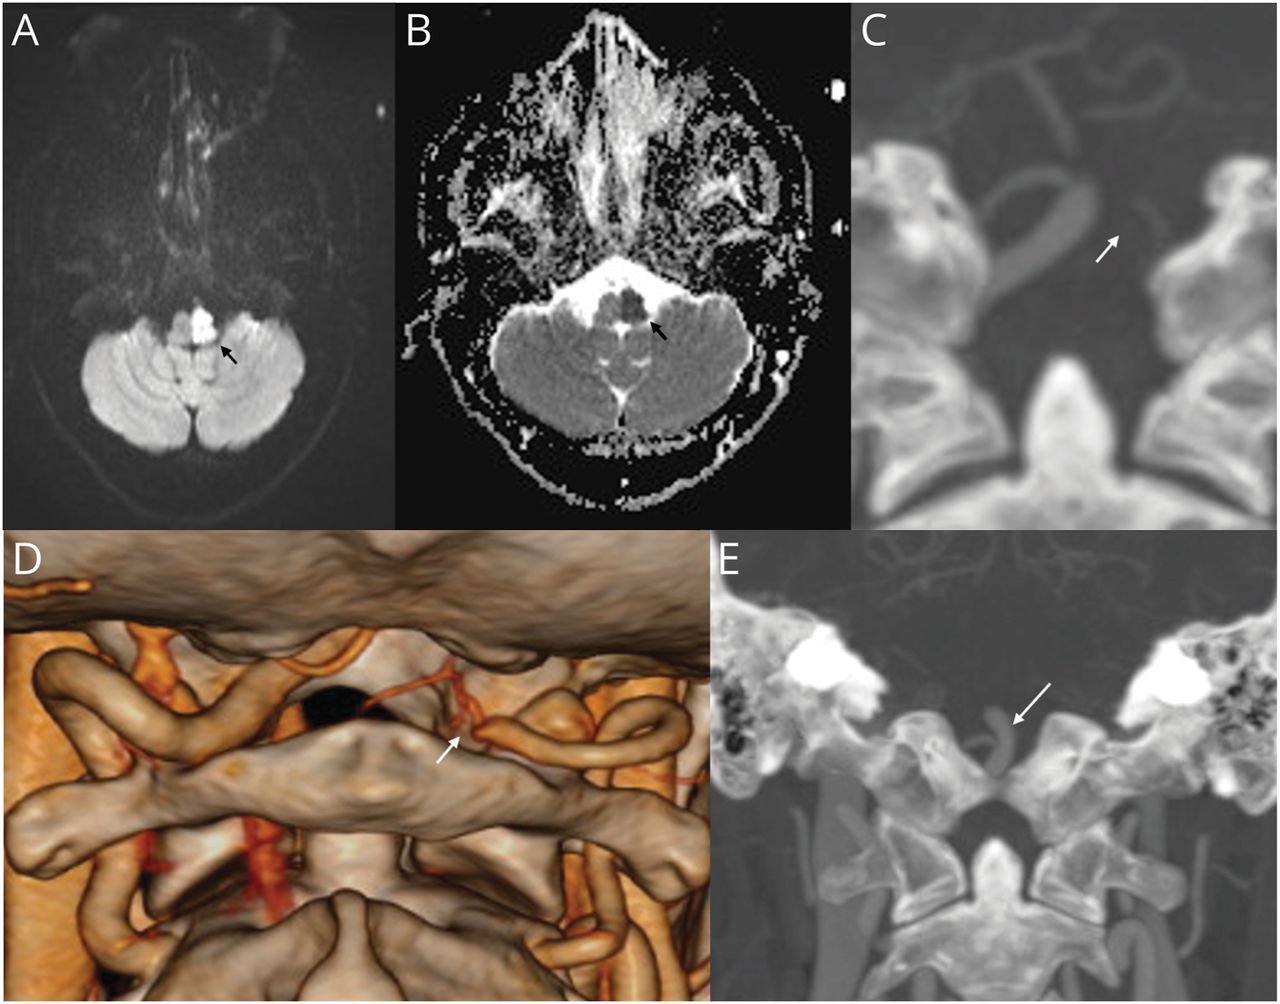

32岁男性,无血管危险因素,急性起病眩晕,吞咽功能障碍,右侧无力。体格检查显示左侧有以下体征:霍纳综合征;下运动神经元第9、10、12脑神经麻痹;小脑肢体共济失调;面部疼痛和体温下降;面部,躯干和四肢的精细触觉和本体感觉丧失。在右侧,他有偏瘫,躯干和四肢疼痛和体温下降。脑核磁共振显示急性脑梗塞累及髓质左半部(图,A和B).头颈部血管CT造影显示左椎动脉V4段闭塞(图C, D, E).诊断为Reinhold完全性半髓质综合征(表格).1,-,3.几乎类似的Babinski-Nageotte不完全半髓样综合征缺乏同侧舌下神经麻痹。2中风病因检查显示正常的糖化血红蛋白,血脂,阴性的高凝,自身免疫和血管炎组。超声心动图正常,长时间心脏遥测未见心律失常。他维持乙酰水杨酸100 mg,每日1次,夜间阿托伐他汀40 mg,用于二次卒中预防。

脑非对比MRI显示扩散加权成像显示高信号累及左半脑(A;黑色箭头),在表观扩散系数序列(B;黑色箭头),提示急性梗死。冠状位CT脑血管造影显示左椎动脉V4段未显示(C;白色箭头)和完整的基底动脉远端血流(E;白色箭头)。三维阴影表面显示体绘制(SS-VRT)重建图像显示左椎动脉V4段突然闭塞(D;白色箭头)。